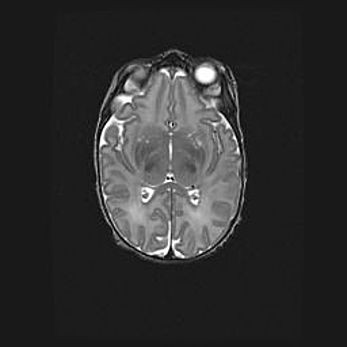

Подострая гематома правой гемисферы мозжечка.

Наружная гидроцефалия.

Возраст: 15 дней

Вес: 3100 г

Пол: женский

Окружность головы: 37 см

Срок гестации: 35-36 недель

При открытой наружной форме гидроцефалии у новорожденных расширяются и переполняются субарахноидные пространства.

Кровоизлияния в мозжечок имеют две клинико-анатомические формы: полушарные гематомы и кровоизлияния в червь.

К появлению этой патологии может привести: повреждения головного мозга, возникающие в результате асфиксии и гипоксии плода при беременности, или травмы во время родов. Редко гематома мозжечка может быть результатом первичной коагулопатии и сосудистой мальформации, диссеминированном внутрисосудистом свертывании, изоиммунной тромбоцитопении.